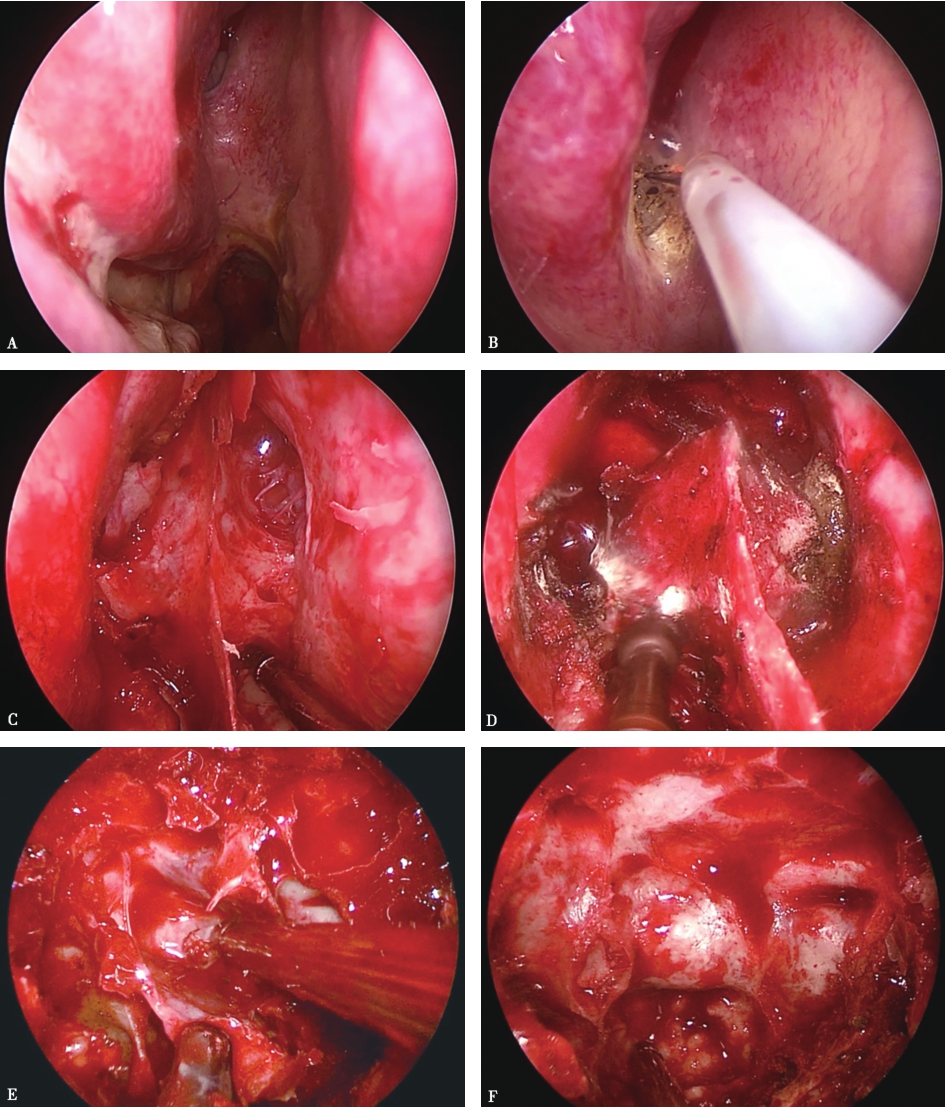

图1手术过程

A.内镜下显露右侧鼻腔,通过定位后鼻孔上方的鼻中隔与中鼻甲之间蝶筛隐窝来确定蝶窦开口的位置;B.用电刀从蝶窦开口开始切开鼻黏膜,行鼻中隔黏膜瓣成型,黏膜瓣的蒂部留在中上鼻甲根部内侧的蝶筛隐窝处,此处有蝶腭动脉的分支鼻后中隔支,供应整个鼻中隔黏膜的血供,即可供应带蒂的鼻中隔黏膜瓣,作为颅底重建的血运来源;C.黏膜瓣制备后,去除骨性鼻中隔的根部,显露整个蝶窦前壁,向上显露到蝶窦开口以上,向下显露蝶窦喙部;D.用高速磨钻将蝶窦前壁磨除;E.进入蝶窦腔后,可见蝶窦腔内有数量不等、不规则的骨性分隔,分隔及蝶窦表面均有黏膜覆盖,去除黏膜和骨性分隔,清晰显露蝶窦后壁的结构;F.在蝶窦后壁上,可以观察到的结构有鞍底、斜坡、双侧颈内动脉隆起、海绵窦隆起、视神经管隆起、视神经管-颈内动脉隐窝、鞍结节等。显露更多的正常结构有助于判断鞍底的位置,因为若蝶窦气化不良或者蝶窦气化太好,均有可能导致定位失误。蝶窦气化不好可能会导致无法判断鞍底位置,蝶窦气化太好,有可能将颈内动脉隆起、视神经管隆起误认为是鞍底,导致手术并发症。可借助于C型臂、导航来定位,增加手术的安全性。